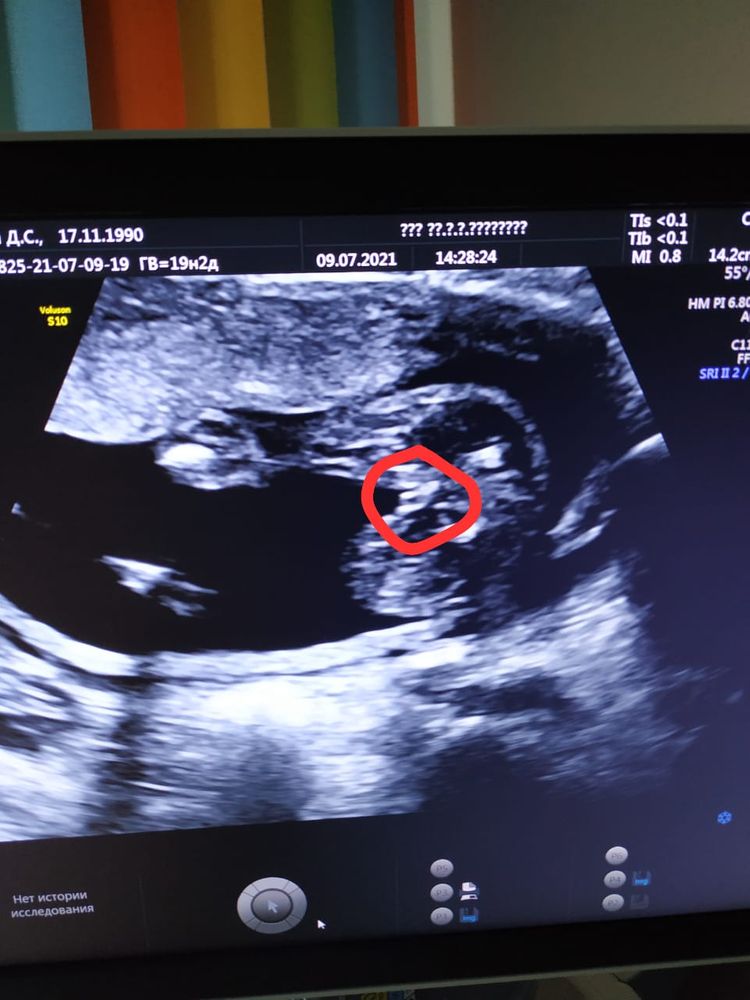

Могут быть сомнения?

Поверьте моему опыту 😂 У вас доченька 👸

Доченька

Принцесса))